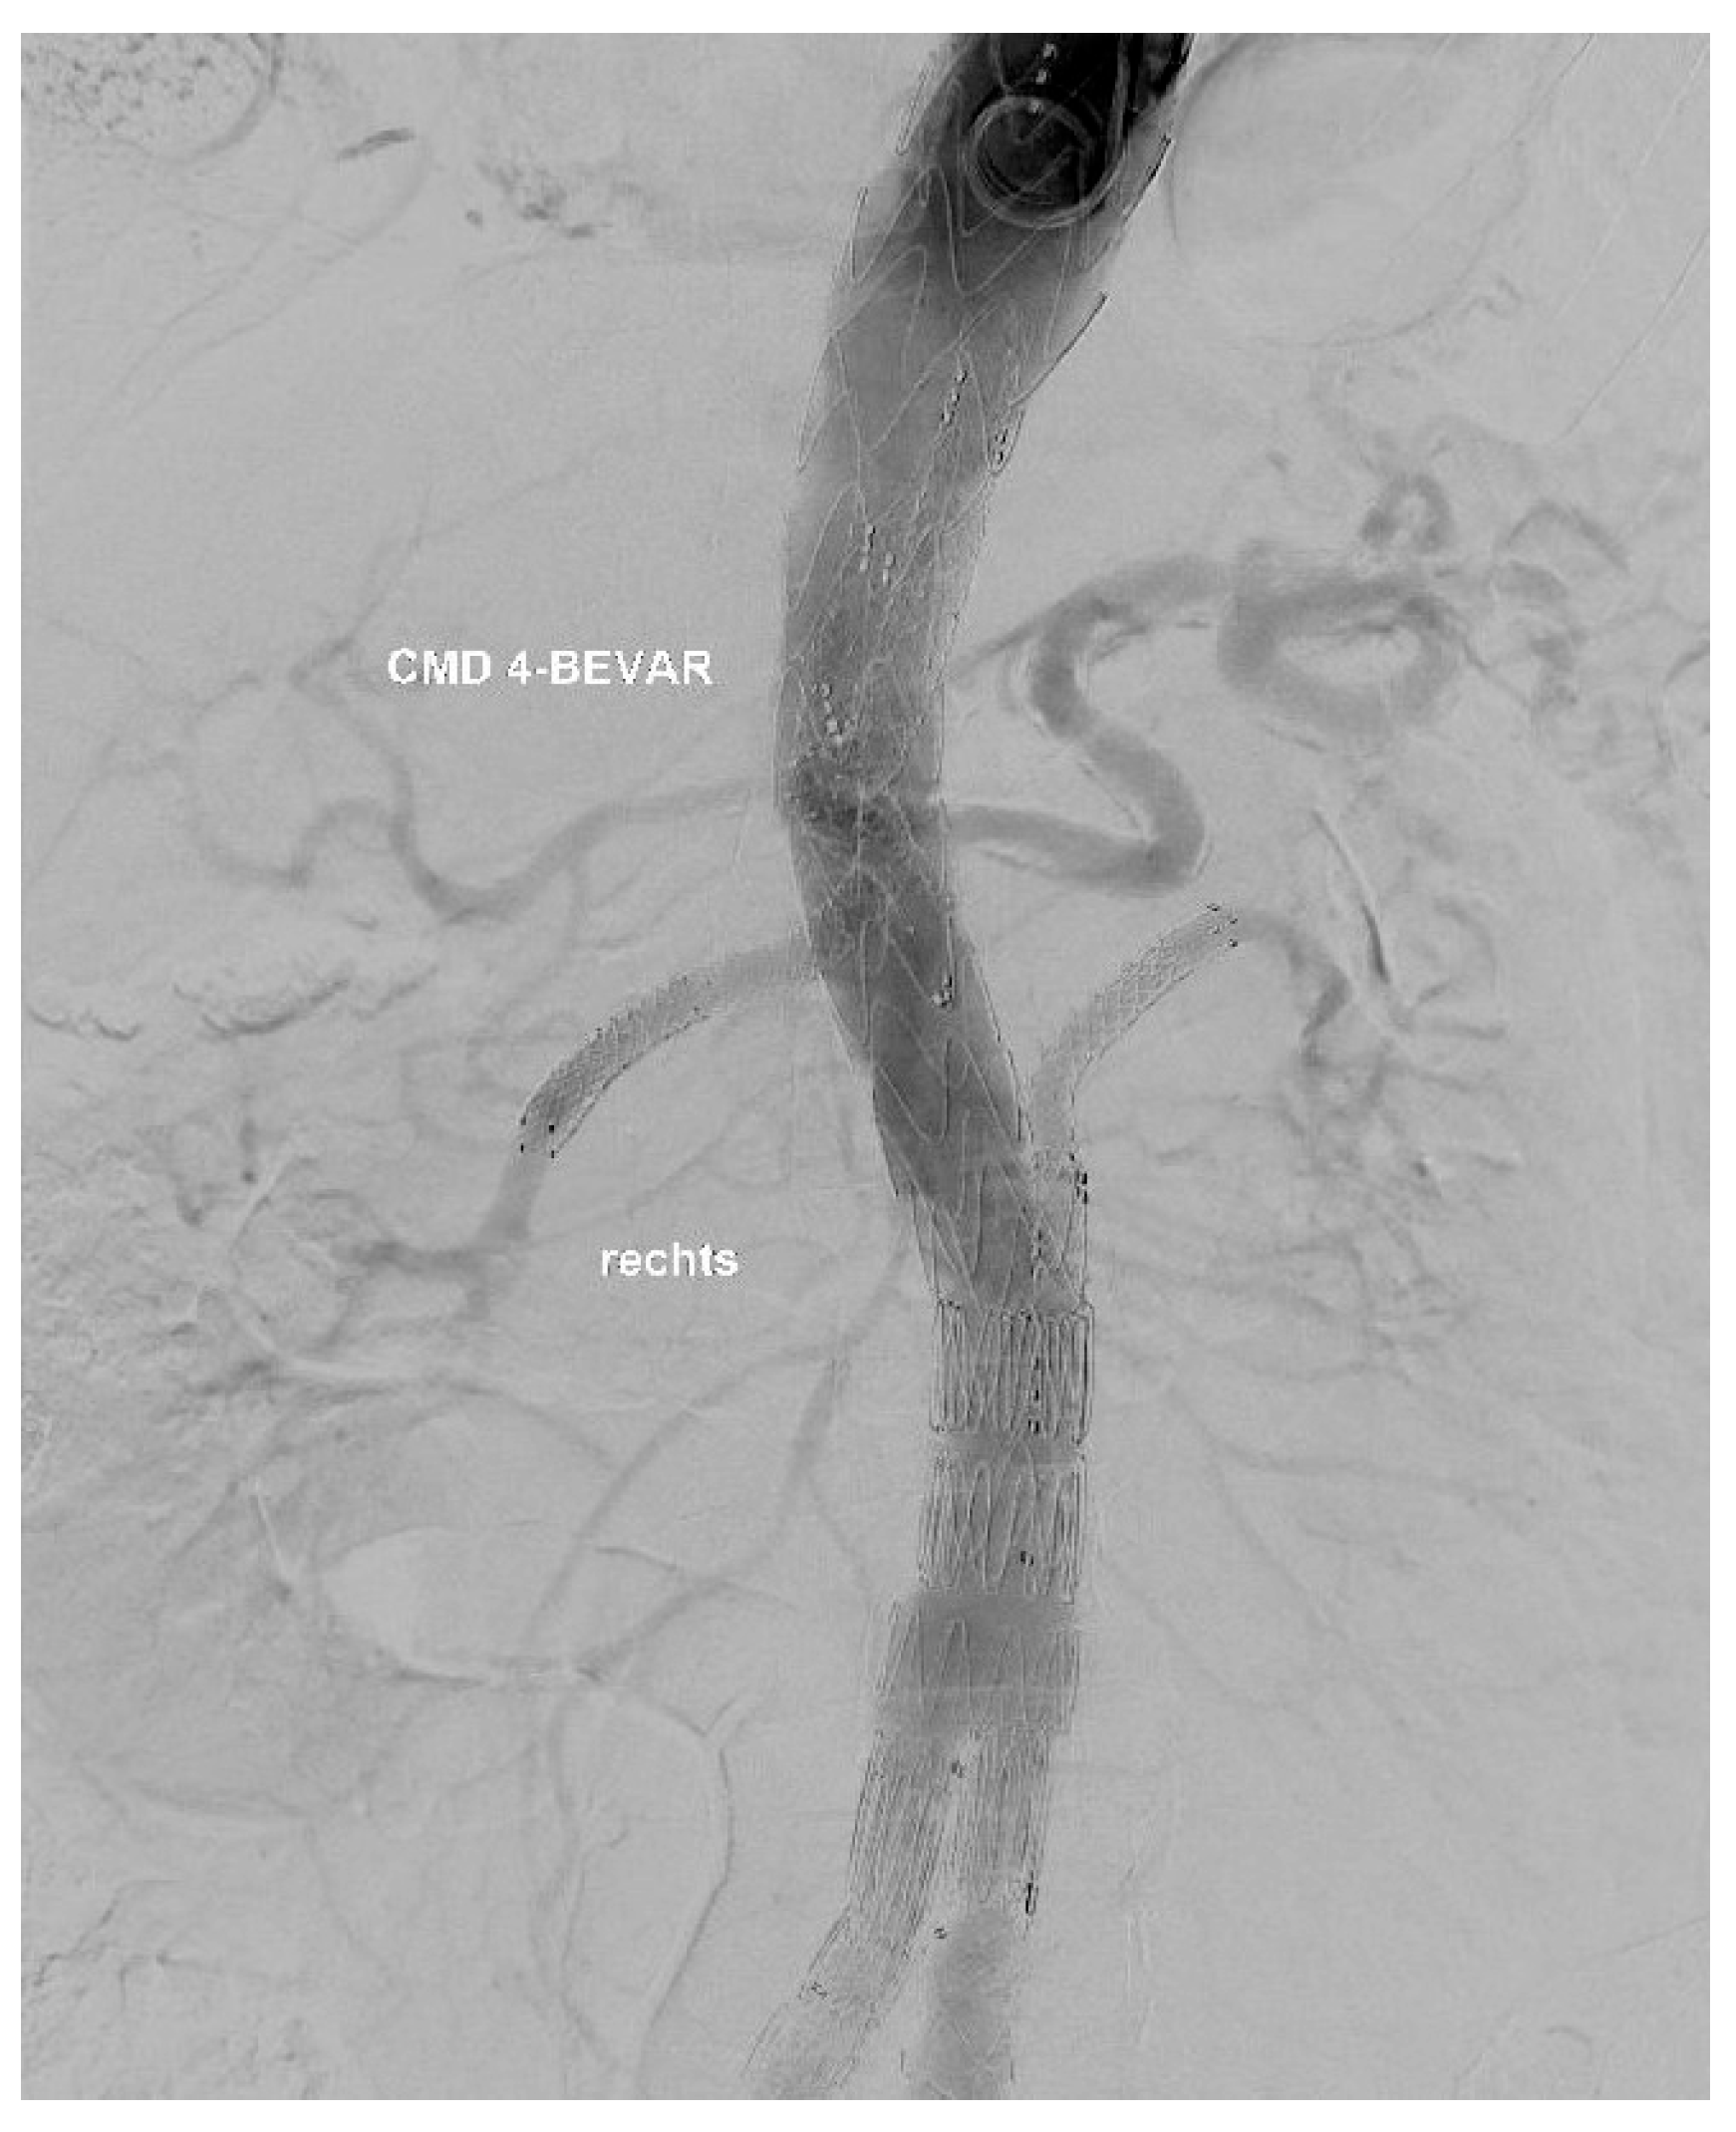

The target vessel of the upward-facing branch was always at least one of the renal arteries (Figure 2). In two cases, both renal arteries were connected through upward-facing branches, and in one case, we used it for an accessory renal artery.

At the end of every operation, an angiography was performed to obtain an overview regarding if the BSGs are patent and if there is any sign of an endoleak of any type (Figure 3 and Figure 4).

Figure 2. XA during the procedure.